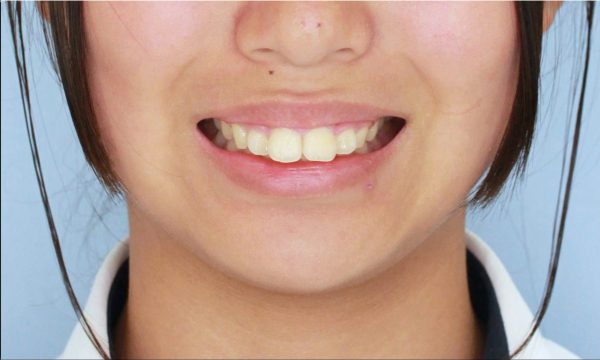

前歯が 出ています。 典型的な ”出っ歯” の状態です 少し段差もあります

前歯が 強く傾斜して、骨ごと 前に 出ています

上顎前突症(いわゆる 出っ歯)です

真横から 見るとよくわかりますね